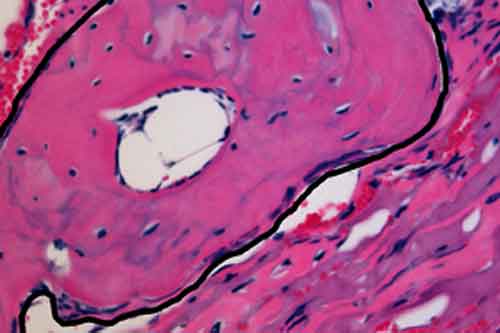

Una nuova scoperta a proposito di cellule staminali potrebbe portare a nuove terapie per la riparazione delle ossa.cellule_staminali Gli scienziati della University of Southampton hanno creato un nuovo metodo per generare cellule ossee: il trattamento potrebbe portare a un nuovo metodo rivoluzionario per riparare le fratture ossee che attualmente necessitano di applicazione di protesi.

Come si legge sulla rivista Small, gli scienziati hanno coltivato cellule staminali embrionali sulla superficie dei materiali plastici e hanno poi valutato lo loro capacita’ di cambiare. I ricercatori hano usato un pattern nanotopografico su platica biomedica per manipolare le staminali cellulari embrionali e trasformarle in cellule ossee. Il materiale ottenuto offrira’ un modo accessibile ed economico per coltivare staminali embrionali umane ossee e offrira’ nuove opportunita’ per la ricerca medica in questo settore.